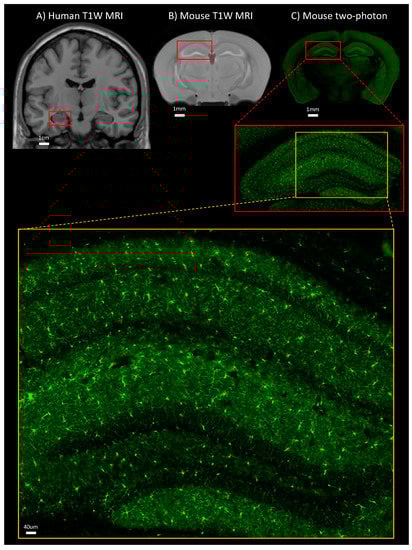

2. MR Imaging of the Brain in Obesity

3. Microscopy Imaging of the Brain in Obesity

3.1.2. Modalities Employed